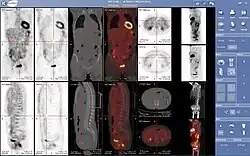

W niektórych centach medycyny nuklearnej nakłada się skany przy wykorzystaniu oprogramowania lub ulepszonych detektorów. Używa się tomografii komputerowej lub rezonansu magnetycznego, aby uwydatnić część ciała pacjenta, która jest obiektem badania z dziedziny medycyny nuklearnej. Wyłaniają się z tego metody PET-MRI, PET-CT i SPECT-CT, które wykorzystują skanery hybrydowe składające się z połączenia skanerów PET/SPECT z tomografami komputerowymi.

Skan całego ciała metodami PET-CT i SPECT-CT wykorzystuje się zazwyczaj do wykrywania różnych rodzajów raka. Można dzięki temu wykryć przerzuty, powiększanie się ogniska pierwotnego lub też nawrót choroby. Nieprawidłowy skan ciała uwydatnia wiele przerzutów raka, a badanie takie umożliwia podjęcie skutecznych kroków aby przeciwdziałać dalszemu postępowi choroby.